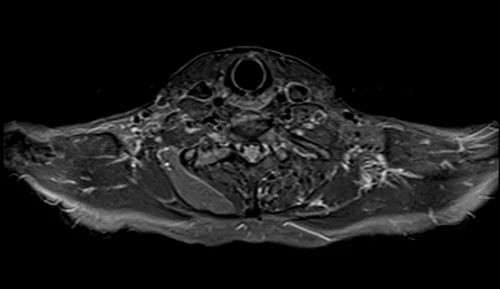

MRI brachial plexus axial STIR images